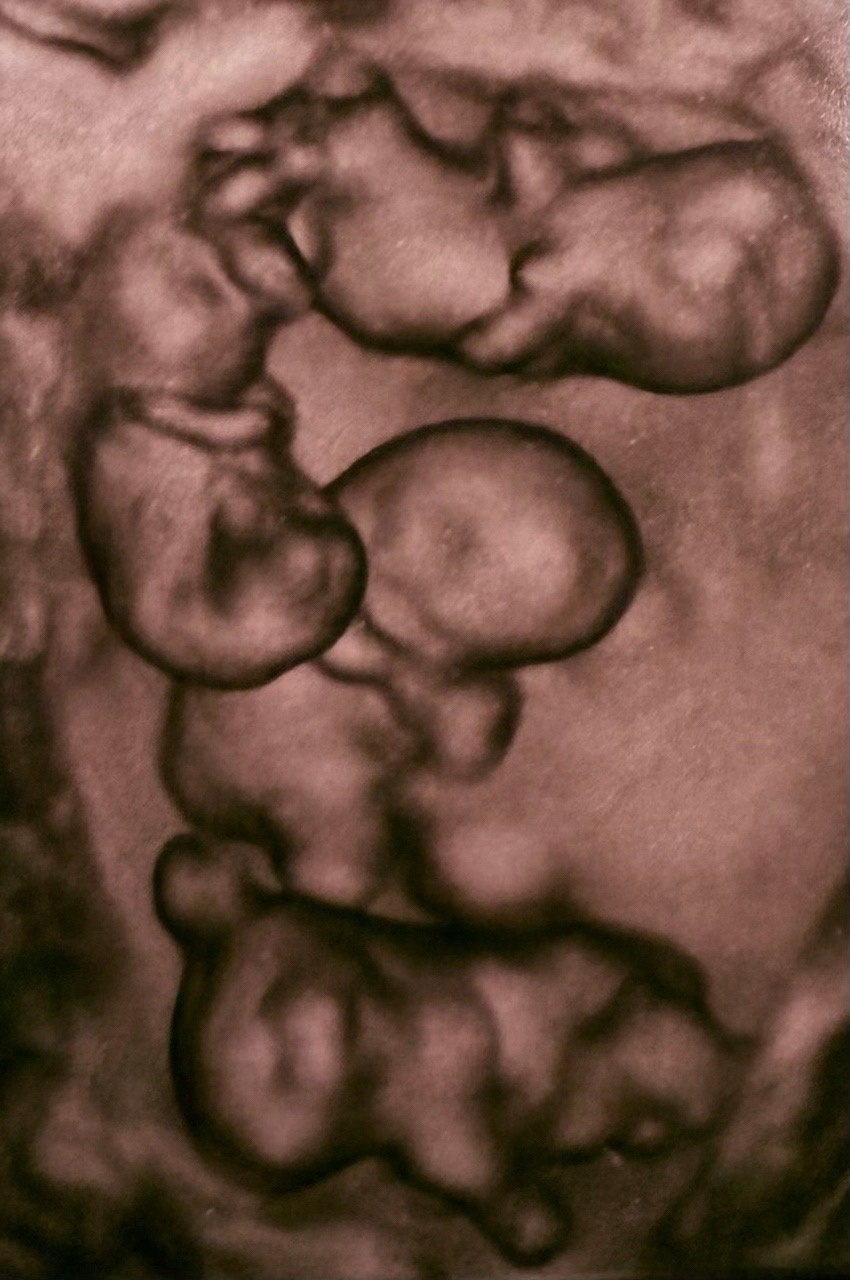

«На сроке 32 недели на свет появились четыре очаровательные сестренки. По расчетной статистике, монохориальная, однояйцевая, четверня — один случай на 15,5 млн родов. В стране не описано таких уникальных родов», — пишут в группе Санкт-Петербургского роддома №17 во «ВКонтакте».

Вес новорожденных составил от 1,36 до 1,64 кг, рост — от 37 до 41 см. Специалисты оценили состояние детей как хорошее с учетом срока беременности.